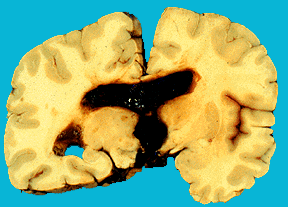

Рис. 1 Субдуральная гематома.

Субдуральные кровоизлияния всегда имеют травматическую природу. Источником их являются вены, впадающие в верхний сагиттальный синус, сосуды мозжечкового намета. Супратенториальные субдуральные кровоизлияния характеризуются нарастанием гипертензионно–гидроцефального синдрома через 2-4 дня "светлого промежутка", мидриазом на пораженной стороне, стойкой девиацией глазных яблок в сторону поражения, гемипарезом на противоположной стороне, судорогами, комой, выбуханием и пульсацией родничков, брадикардией, нарушением терморегуляции.

При нераспознанной гематоме через 7-10 дней происходит ее инкапсуляция с последующей атрофией мозговой ткани. Лечение нейрохирургическое. Субтенториальные субдуральные кровоизлияния (кровоизлияния в заднюю черепную ямку) характеризуются особой тяжестью. С момента рождения нарастают симптомы сдавления ствола мозга: ригидность затылочных мышц, анизокория, стойкое отведение глаз в сторону, грубый нистагм, тонические судороги. Прогрессируют брадикардия, расстройство дыхания, вялость, гипо- и арефлексия, расстройство сосания и глотания.

Тяжесть и прогноз определяются своевременностью диагностики и нейрохирургического лечения. Возможен благоприятный исход, но с последующим появлением гидроцефалии, минимальной мозговой дисфункции.

Лечение: поверхностная субдуральная гематома дает благоприятный исход, если своевременно произведен субдуральный прокол, удалена кровь и снижено внутричерепное давление. Хирургическое лечение необходимо, если прокол неэффективен.

Разрыв мозжечкового намета составляет 90-93% смертельных родовых травм. может быть одно- и двусторонним, полным и неполным (разрывается только верхний листок, излившаяся кровь при этом располагается супратенториально), при полном - супра- и и инфратенториально (в средней и задней черепной ямках). Субдуральные кровоизлияния в средней черепной ямке наблюдаются также при разрывах нижних мозговых вен, впадающих в поперечный синус, разрывах поперечного синуса. Субдуральные кровоизлияния, располагающиеся на своде мозга и в верхней продольной щели, обусловлены разрывом серпа (2,5-8% смертельных родовых травм), верхних мозговых вен, впадающих в верхний сагиттальный синус. Особенно массивные субдуральные кровоизлияния в продольной щели мозга бывают при разрыве большой вены мозга (вены Галена). При этом возникают также субарахноидальные кровоизлияния, а в случае затекания крови в желудочки мозга - внутрижелудочковые. Если кровоизлияния массивные, смерть наступает интранатально или вскоре после рождения. При субдуральных кровоизлияниях кровь может затекать под твердую мозговую оболочку спинного мозга, а из желудочков - в спинномозговой канал.